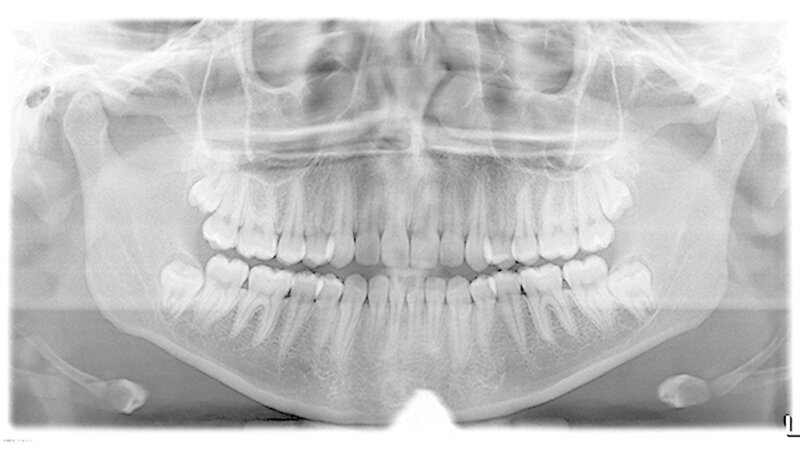

Somit konnte auf eine Verplattung mittels Osteosynthese-Material verzichtet werden. In alle Extraktions-Alveolen wurde Gelatamp, Firma Roeko, eingebracht. Der Nahtverschluss erfolgte atraumatisch mit Vicryl 3/0, Firma Ethicon. Zur Dokumentation wurde postoperativ ein digitales OPG angefertigt.